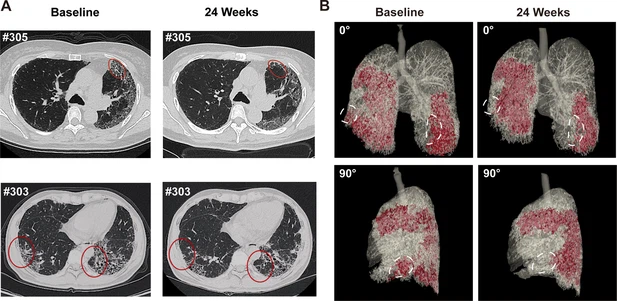

• 蜂窩狀病變消退:1M劑量組中兩名患者(#303、#305)的HRCT顯示下葉蜂窩狀病變減少(圖4A),三維重建證實(shí)下葉病變區(qū)域縮小(圖4B)。

圖4:REGEND001治療前后的代表性肺部CT圖像。

(A) 患者#305和#303在基線和REGEND001治療后24周的代表性肺部CT圖像。紅色圓圈表示蜂窩狀病變消退。(B) 患者#305連續(xù)CT圖像的三維可視化。紅色區(qū)域表示細(xì)胞治療前后肺部受損區(qū)域(網(wǎng)狀和蜂窩狀)。白色圓圈表示下葉病變消退。